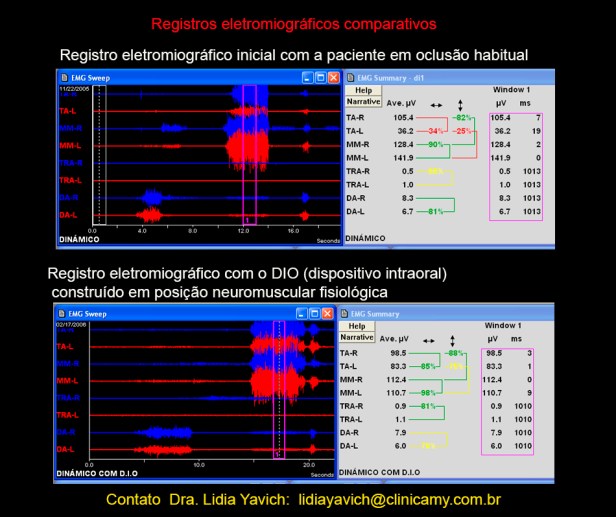

Neste registro eletromiográfico do paciente em oclusão habitual é gritante a diferença entre os temporais anteriores direito e esquerdo.

Existe quase 70 por cento de diferencia entre o temporal esquerdo e o direito em oclusão máxima habitual.

O temporal anterior direito consegue gerar 105 microvoltios na faixa analisada já o temporal anterior esquerdo consegue gerar só 36 microvoltios, na mesma faixa.

Registro eletromiográfico do paciente em oclusão neuromuscular fisiológica com o dispositivo em boca: os temporais anteriores direito e esquerdo estão equilibrados.

O registro inicial em oclusão habitual registrava quase 70 por cento de diferencia entre o temporal esquerdo e o direito em oclusão máxima habitual.

Registros eletromiográficos comparativos: o superior em oclusão habitual e o inferior em oclusão neuromuscular fisiológica com o DIO (dispositivo intraoral) em boca.